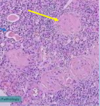

Adenocarcinoma of colon

MALIGNANT TUMOR formed of irregular acini infiltrating the submucosa and muscle layer. Malignant cells vary in size and shape

Red: normal mucosal glands Black: Malignant glands

Malignant